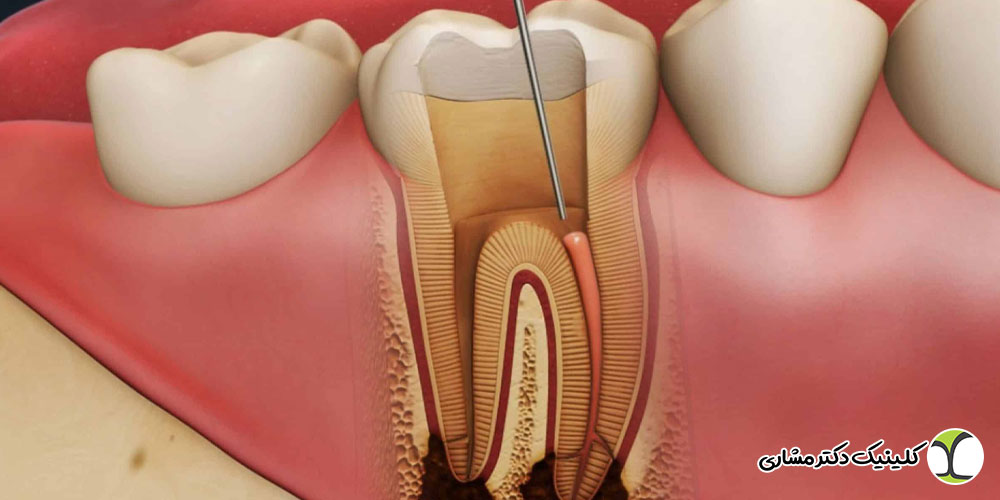

درمان مجدد ریشه یا ری اندو، فرایندی است که طی آن دندان قبلاً عصبکشی شده دوباره باز می شود و مواد پرکردگی کانال ها خارج شده، کانال ها پاکسازی و ضدعفونی شده و مجدداً پر می شوند.

این فرایند معمولاً توسط متخصص اندودنتیست انجام می شود و به دلیل پیچیدگی آن، نیازمند تجهیزات پیشرفته و مهارت بالای دندانپزشک است. هدف اصلی درمان مجدد رفع عفونت و اصلاح مشکلات درمان اولیه است تا دندان حفظ شود و نیازی به کشیدن آن نباشد.

تورم لثه یا تشکیل کیست در انتهای ریشه

تورم لثه اطراف دندان یا تشکیل کیست های کوچک و بزرگ در انتهای ریشه نشانه ای از عفونت فعال یا تجمع چرک است. این وضعیت معمولاً با درد، حساسیت به لمس و گاهی بوی ناخوشایند همراه است و با رادیوگرافی مشخص می شود. درمان مجدد ریشه در این شرایط برای جلوگیری از گسترش عفونت و حفظ دندان ضروری است.

آمادگی و برنامه ریزی درمان: اگر درمان مجدد ریشه انتخاب شود، معمولاً ابتدا پوسیدگی ها و ترمیم های قبلی برداشته می شوند و مسیر ورود به کانال ها ایجاد می گردد. سپس مواد پرکردگی قدیمی خارج شده و کانال ها با وسایل مخصوص شکل دهی و تمیز می شوند تا عفونت و باکتری ها به طور کامل از بین بروند.

پر کردن مجدد کانال ها و ترمیم تاج دندان: پس از پاکسازی کامل کانال ها، آنها با مواد مخصوص (مثل گوتاپرکا) پر می شوند تا ورود میکروب ها به کانال مجدد غیرممکن شود. در نهایت تاج دندان پانسمان شده و برای ترمیم نهایی یا قرار دادن روکش به دندانپزشک مربوطه ارجاع داده میشود.